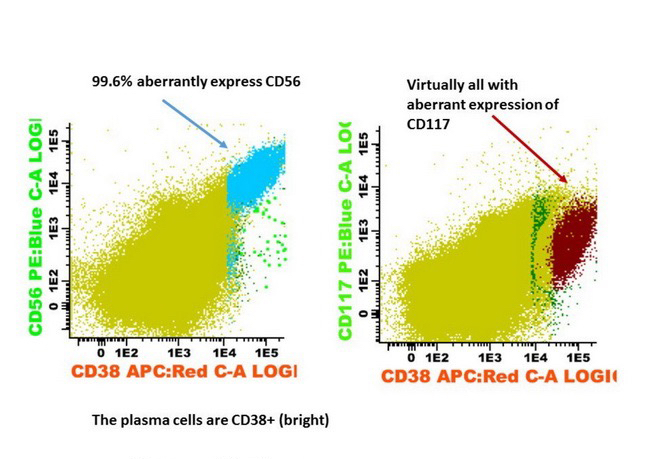

- May have aberrant expression of CD56 (75 - 80%), CD200 (60 - 75%), CD28 (~40%), CD117 / KIT (20 - 35%), CD20 (10 - 20%), CD52 (8 - 14%), CD10 and occasional myeloid or monocytic markers; may correlate with cytogenetics in some cases (Leuk Lymphoma 2015;56:426, Cytometry B Clin Cytom 2016;90:61)

Flow cytometry description

- Monotypic cytoplasmic Ig and usually lack surface light chain

- Express CD38, CD138, often CD56+ or CD117+; may have partial CD45, usually negative for CD20, CD19 and CD10 (Cytometry B Clin Cytom 2016;90:61)

Flow cytometry images